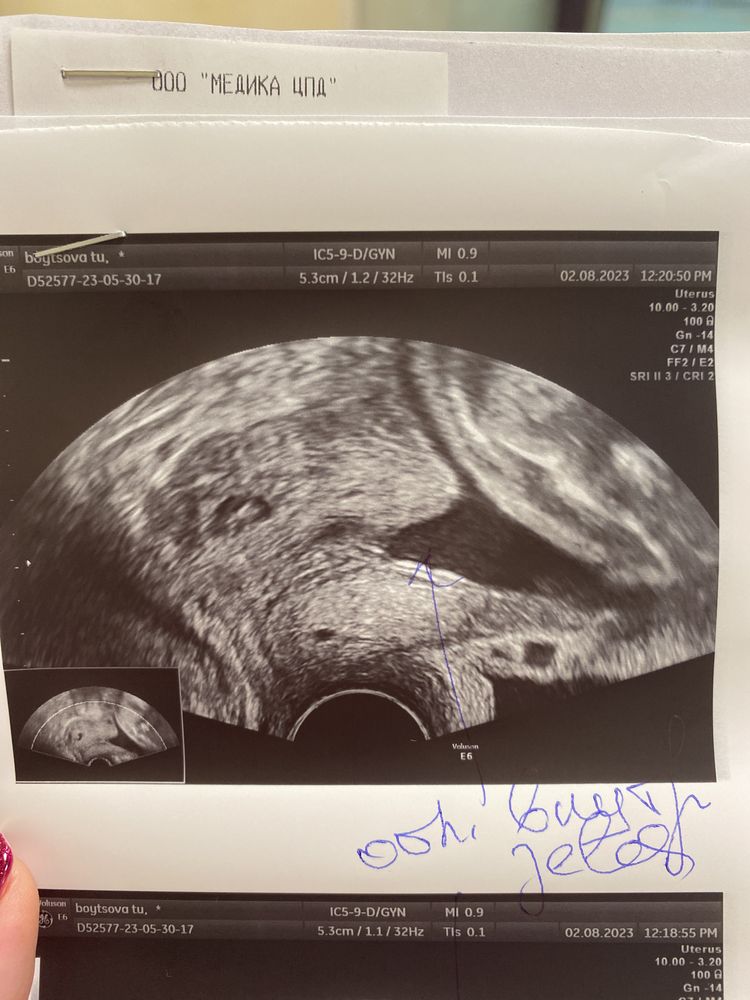

28 недель и здравствуй пессарий (фото)